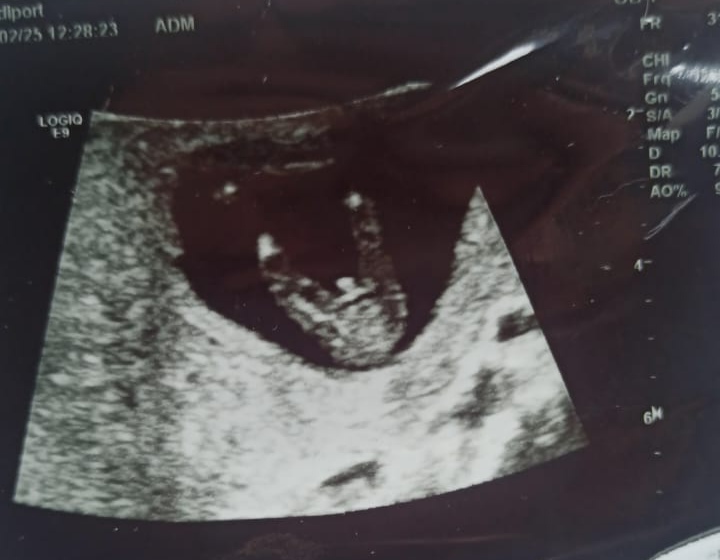

Мальчик или девочка?? 12 недель 4 дня

Общим консилиумом 7ых Узистов + 3 врача Решили и твёрдо поставили жирную точку- у нас будет мальчик. Клиника также провела УЗИ обследование, их врач по размеру плода определили что уже 13 недель и 4 дня и сами чётко увидели , что у девочки такого клитора быть не может...говорят крупный и хорошо развивающий плод Итог: клиника принесла извинения и готова за эту цену сделать нам расширенный НИПТ, но я им уже не доверяю, и забрала свои денежки обратно. Изображение Изображение